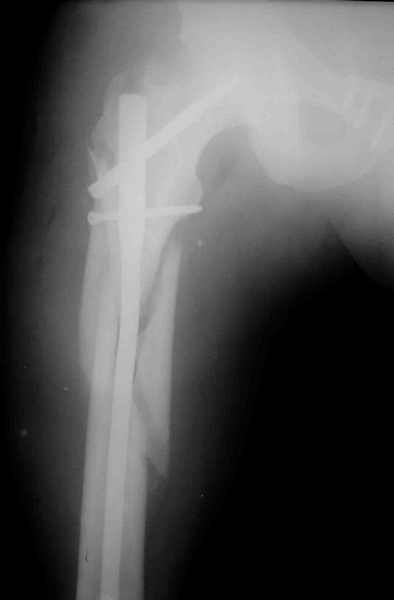

Вот вариант решения похожей ситуации